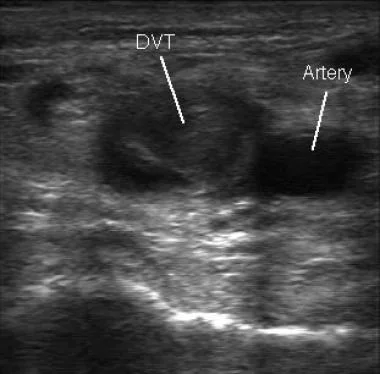

Venous Duplex Ultrasound: results are positive for deep vein thrombosis (DVT)